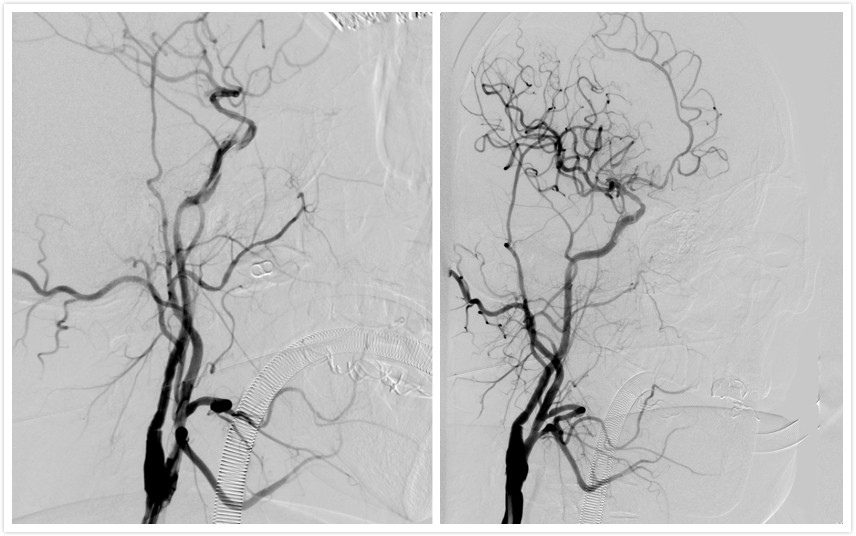

患者男性71岁,因“头晕伴左侧肢体无力3月”入院,就诊于我院神经外科。头颅CT提示:1.多发腔隙性脑梗塞2.右侧基底节及外囊区梗塞。行全脑血管造影(DSA)提示右侧颈内动脉起始段闭塞,颅内段血管显影不佳。患者高龄,既往有高血压、糖尿病、高脂血症、心脏病等、病情复杂。如不及时予以治疗,将可能发展为大面积脑梗塞,危及生命。王晓健副主任医师团队详细分析患者资料后,结合相关文献并借鉴国内先进单位成熟技术,决定对患者实施闭塞颈动脉开通术(CEA+颅内外支架植入的复合手术)。切开颈内动脉,剥除斑块,同时在颈内动脉狭窄段放入支架。术后造影显示闭塞动脉开通满意,血管通畅,患者恢复良好,3—4天后即可在辅助下行走,一周后就已顺利出院。

术前DSA